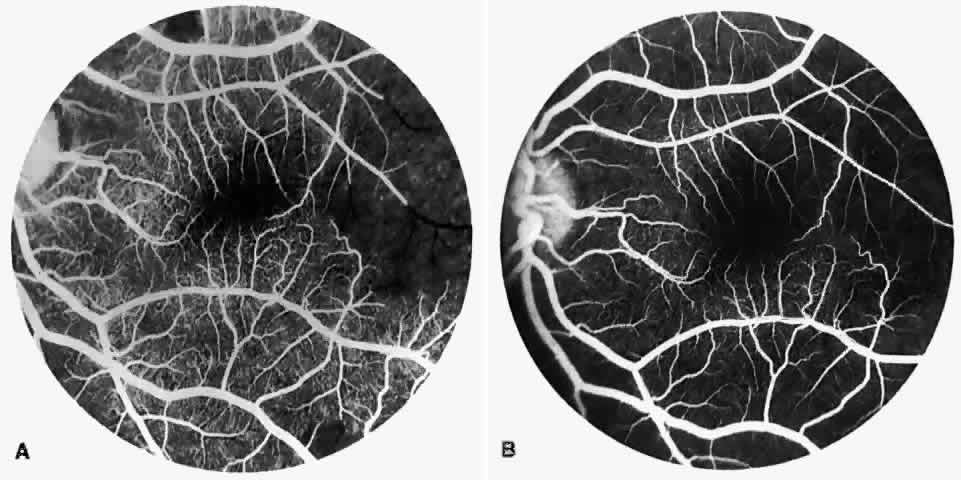

PSR is associated with the severe vision-threatening sequelae of sickle cell disease: vitreous hemorrhage (stage IV) and retinal detachment (stage V). These stages are believed to result from transudation of blood components into the vitreous through the incompetent neovascular tissue (Fig. 28). Vitreous fluorophotometry has quantified the leakage from the peripheral neovascularization.134 This leads to premature syneresis and collapse of the vitreous, inducing tractional forces on the retina that lead to vitreous hemorrhage, retinal tears, and tractional and rhegmatogenous retinal detachment. In rare cases, an exudative detachment may occur.

|

Spontaneous nonperfusion or autoinfarction, accompanied by regression of the neovascular lesion, occurs in 20% to 60% of eyes with PSR.135,136 The peak incidence of autoinfarction is 2 years after the development of PSR. It appears that autoinfarction occurs primarily as a result of (1) occlusion of the feeding arteriole due to traction on the neovascular lesion by contracting vitreous, or (2) occlusion by sickled RBCs. The latter probably is more common in homozygous sickle cell anemia, which is more commonly associated with autoinfarction and complete vascular occlusion.